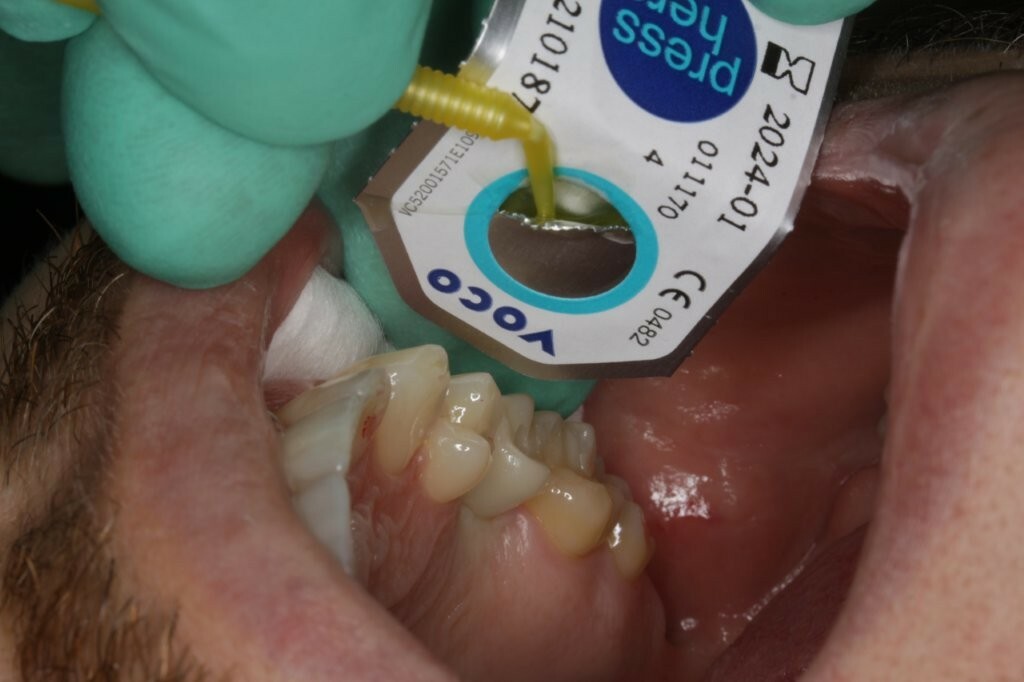

Anschließend wurde das Universal-Adhäsiv Futurabond U (VOCO GmbH) gemäß der Gebrauchsinformation in den Schraubenkanal eingebracht (Abb. 32) und oberhalb des Teflonbands verteilt. Das Lösungsmittel wurde anschließend verblasen und das Adhäsiv mit Licht polymerisiert.